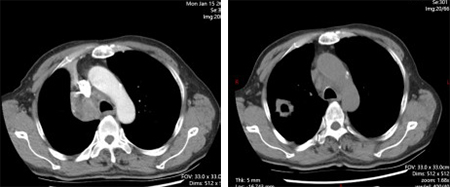

所谓的精准武器,就是当时国内新获批的可医保报销的高选择性MET抑制剂。1月12日,69岁的老李开始口服这种靶向药物——MET抑制剂。仅仅28天,咳嗽、痰血和喘憋就明显减轻。复查CT,原本被肿瘤压瘪的右上肺重新张开,连支气管镜下的“菜花”样新生物也缩小了近一半。老李高兴地说:“睡觉不再被憋醒,走路也能跟上儿子了。”

2024年7月,老李的右上肺原发灶增大,支气管再次狭窄。我们立刻给患者复查了气管镜。镜下没有新生物,只有黏膜充血水肿;穿刺也只看到变性坏死组织。影像进展、病理阴性,到底是耐药还是感染?我们启动了全院多学科讨论,最后决定:按耐药处理,执行“化疗+免疫”的二线方案。2个周期后,病灶再次显著缩小,疗效评估达到部分缓解。6周期后病灶继续缩小。老李的咳嗽、憋气症状完全消失,吃得好、睡得香,笑称:“我又回到了没得病的状态。”

靶向治疗前;靶向治疗1个月后

化疗+免疫治疗前;化疗+免疫治疗2周期后